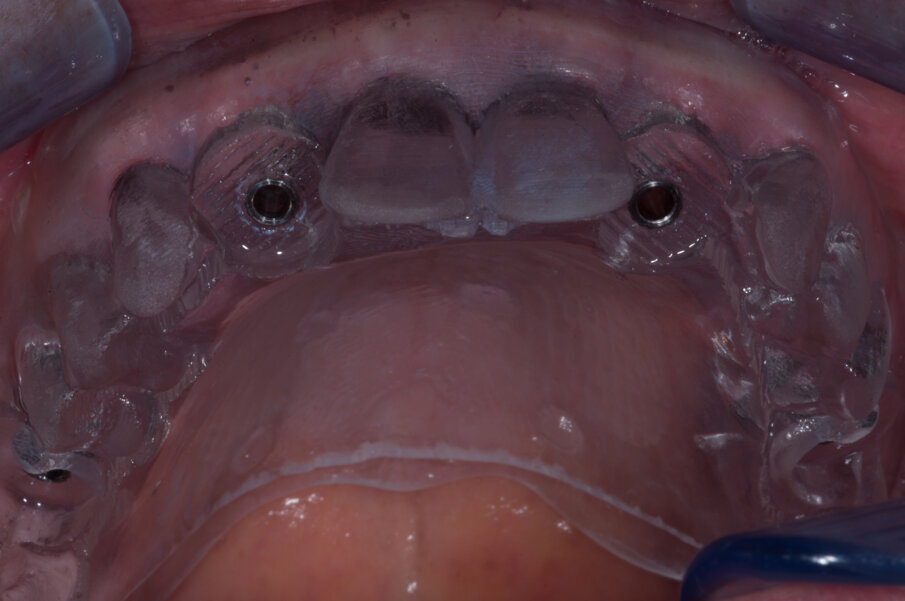

Grazie a questo tipo di pianificazione il software produce una guida chirurgica che viene stampata da una stampante 3D e consente al chirurgo di operare con tecnica “flapless” cioè senza la necessità di aprire dei lembi e causare un maggiore traumatismo al paziente. La guida chirurgica trasparente viene provata in bocca al paziente prima dell’intervento chirurgico per testare la sua stabilità e precisione nel rapporto con i tessuti molli (Figg. 20, 21). In questo caso specifico si era pianificato di utilizzare un nuovo approccio con degli impianti e componenti protesiche particolari, la tecnica “Smart fix” di Astra Tech Implant (Dentsply Sirona) (Figg. 22-25).

I due impianti più posteriori (Astra Tech Implant System EV, Densply Sirona) hanno un design particolare, sono disegnati con un profilo diverso dal normale, con un collare anziché piatto inclinato in maniera tale da consentirne il posizionamento con un asse ed un’angolazione antero posteriore, adattandosi così nella loro emergenza alla cresta ossea (Fig. 22). I due impianti anteriori soni impianti standard, in questo caso con diametro 3,5 mm (Fig. 23). La componentistica protesica prevede MUA (multi unit abutments, multibase Dentsply Sirona) standard sui due impianti anteriori (Fig. 24) e due MUA angolati componibili ed orientabili sui due impianti posteriori (Fig. 25).